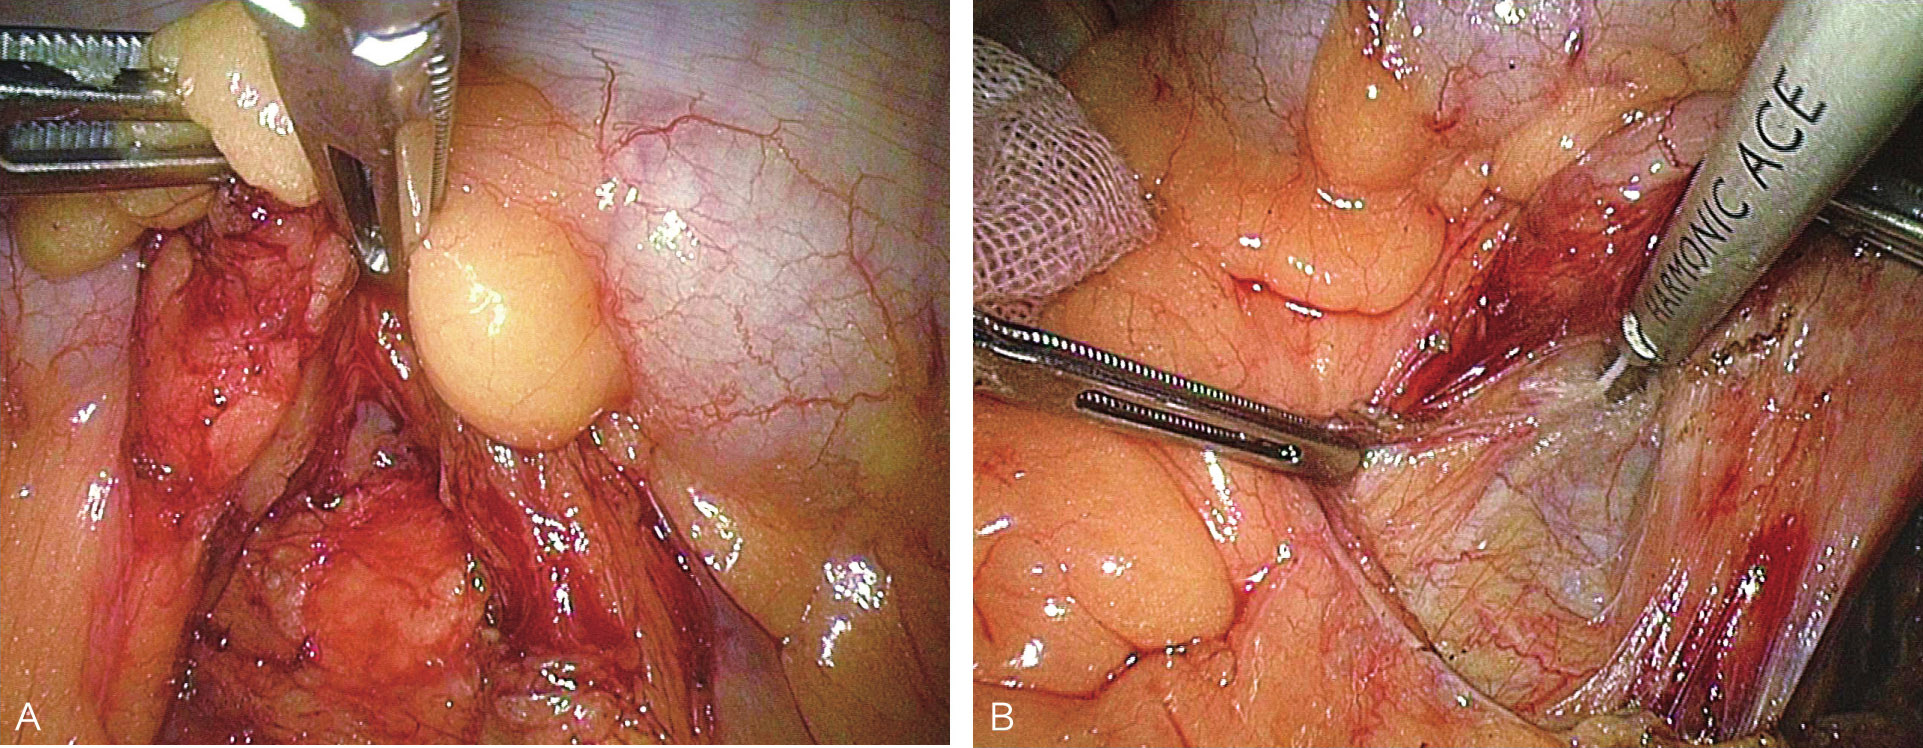

患者取左侧抬高卧位,悬吊左臂,抬高腰桥,取四孔法操作;镜下打开降结肠旁侧腹膜及脾结肠韧带,将结肠脾曲向右下翻起,显露胰尾(图6-16、图6-17);定位肿瘤(图6-18),镜下缝合,牵引下超声刀剜除(图6-19、图6-20),处理创面;取出标本,送冰冻,留置引流,缝闭切口,术毕。

图6-19 完整游离肿瘤

图6-20 肿瘤切除